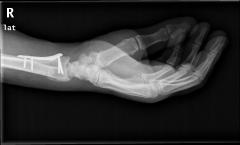

Περίπτωση 1ου ασθενούς